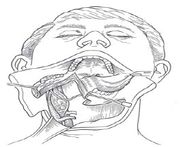

| 04:57, 23 October 2018 | Mandi swing.jpg (file) |  |

77 KB | Drtbalu | |